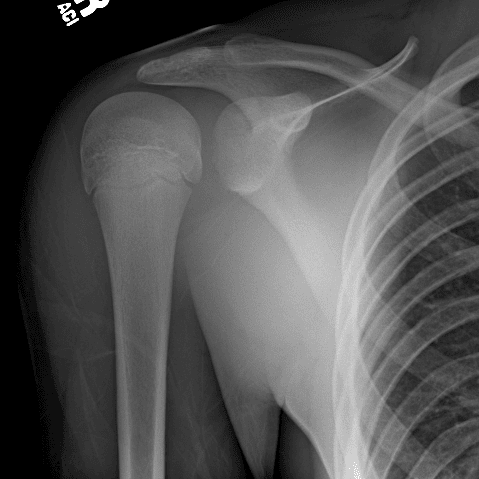

Simuliert den Dienst durch subtile oder schwierige Fälle und einige Normalbefunde.

30 Fälle